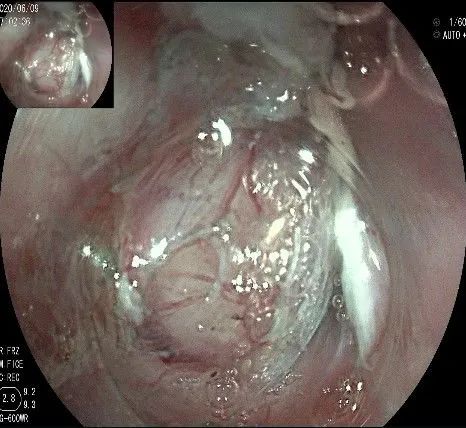

瘤子切除后,在粘膜切开的地方,固有肌层的纵形肌处形成一个开口。

倒镜观察,隆起已经消失。

夹闭创面的时候做胃镜吸引,利于创面闭合。

创面夹闭完成,反复冲洗观察,无出血及穿孔。结束手术,等待病理结果。